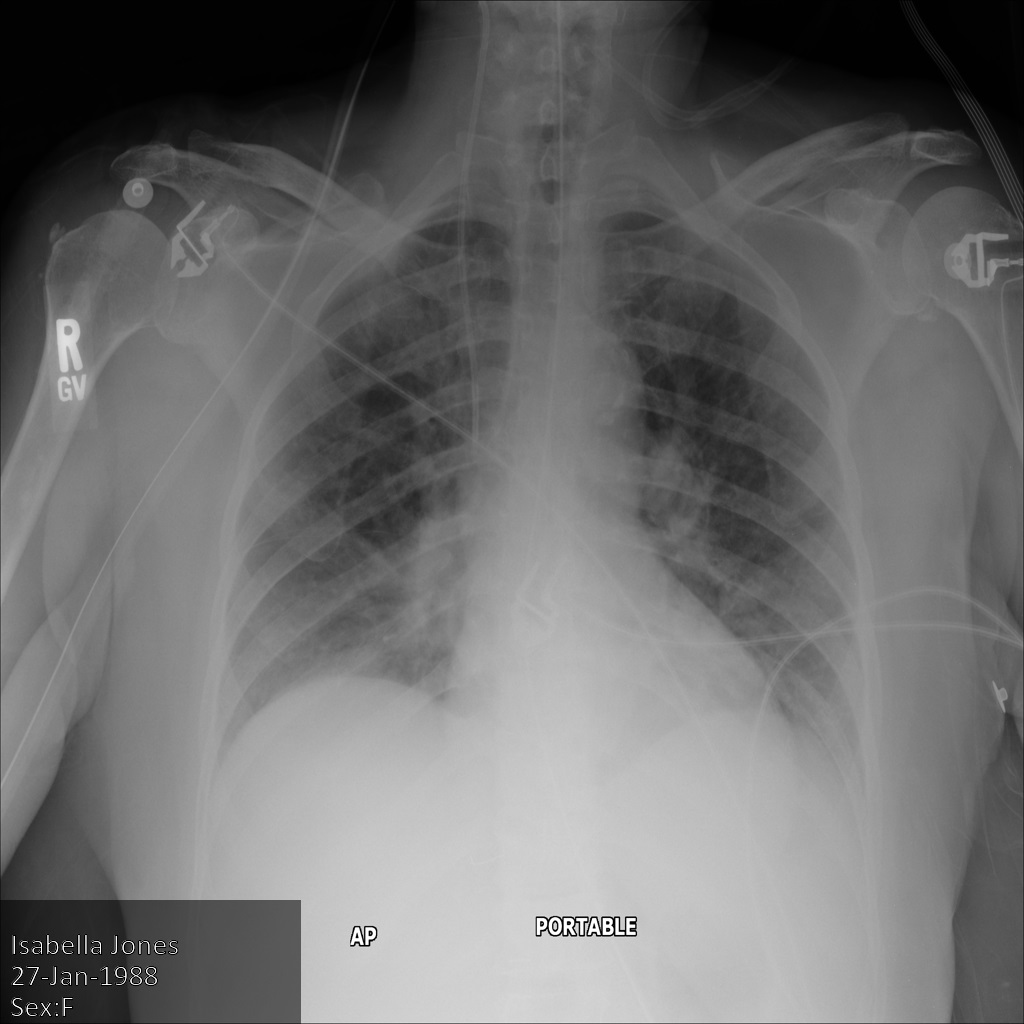

En la siguiente imagen, se muestra una radiografía sin ocultamiento de un paciente:

Después de enviar la imagen a la API de Cloud Healthcare mediante la opción REDACT_SENSITIVE_TEXT, la imagen aparece de la siguiente manera:

Puedes ver que ocurrió lo siguiente:

- Se ocultó el elemento

PERSON_NAMEen la esquina inferior izquierda de la imagen - Se ocultó el elemento

DATEen la esquina inferior izquierda de la imagen

El sexo del paciente no se ocultó porque no se considera texto sensible de acuerdo con los Infotipos de DICOM predeterminados.